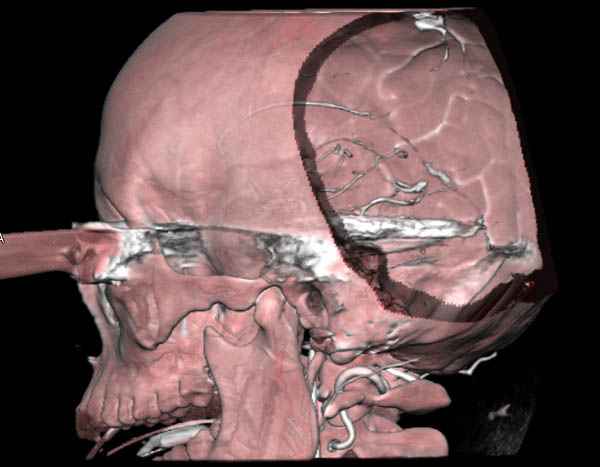

В своих выступлениях я рассказывал, что наши центры в мирное время по пенетрирующим травмам не уступает Ираку или Афганстану, и вот недавно к нам поступила больная 22 лет, травма "ножом в глаз" от бывшей подруги нынешнего "бой френда".

При поступлении в сознании, жаловалась на неприятные ощущения в глазнице.

По протоколу сделаны все необходимые исследования: рентген, ангиограмма с 3Д реконструкцией, где обнаружили что все жизненно важные сосуды не задеты, даже некоторые "сидят" изгибаясь на ноже.

Одним махом нож удалить не удалось, пришлось раскачать и потом двумя руками удалили нож. Рана без кровотечения, обработана и зашита.